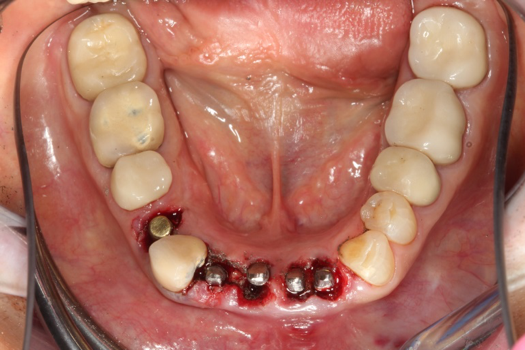

On the day of surgery, the plan was to extract teeth Nos. 21, 23, 24, 25, and 26, place 3.0 x 13-mm implants in the anterior region due to limited spacing, and place a 4.1 x 10-mm implant in the No. 21 extraction site. Before the extractions were performed, the No. 23 pontic was sectioned from the existing 2-unit cantilevered bridge utilizing ceramic and metal high speed rotary cutting burs ZR 6881 and H34L (Komet-USA), respectively. After removal of the pontic and extractions, the surgical guide was verified to be seating positively (Figure 36 through Figure 38). Surgical guide protocol was followed, and all implants were successfully placed and torqued to a value of greater than 35 Ncm (Figure 39 and Figure 40). All implants were placed without flapping, with the exception of No. 23. The flap was elevated to reposition lingual keratinized tissue facially for enhanced esthetic tissue profile. The implants were then prepared with a high-speed carbide bur (Komet-USA) with copious amounts of water (Figure 41 and Figure 42). The one-piece 3.0-mm diameter implant served the needs of the patient's spacing requirements. Inter-occlusal space requirements and path of draw were verified. The PMMA provisionals were air abraded and relined with crown-and-bridge material (Figure 43 through Figure 45).

Fig 42. Occlusal view of prepared implants.

Figure 42

Fig 43. PMMA provisional digitally fabricated and milled.

Figure 43

Fig 44. Splinted PMMA seated.

Figure 44

Fig 45. Occlusal view of seated PMMA provisionals.

Figure 45